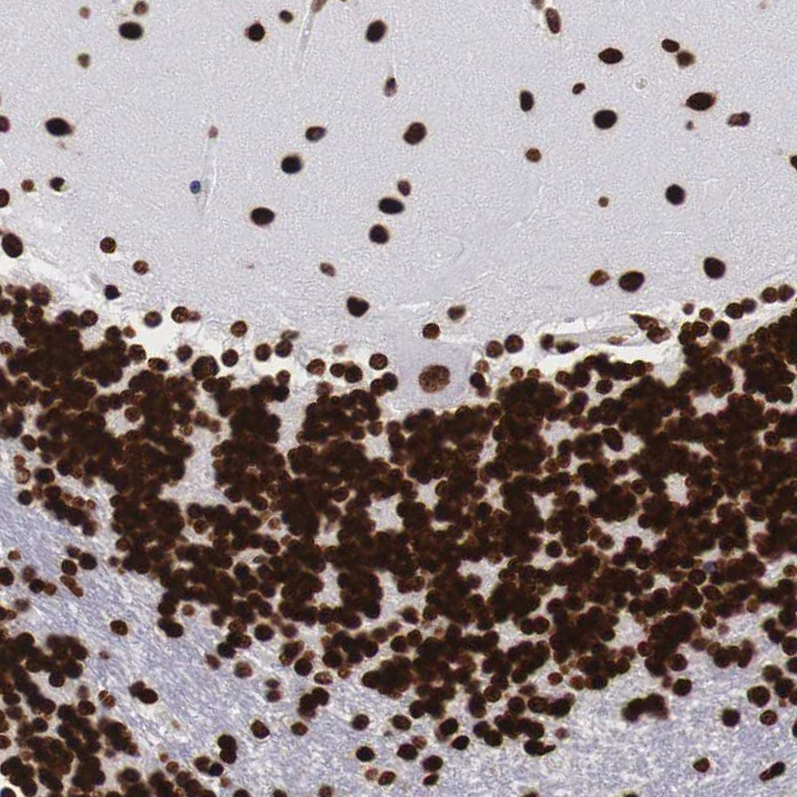

Immunohistochemical staining of human cerebellum, lymph node, prostate and testis using Anti-MECP2 antibody HPA000593 (A) shows similar protein distribution across tissues to independent antibody HPA001341 (B).